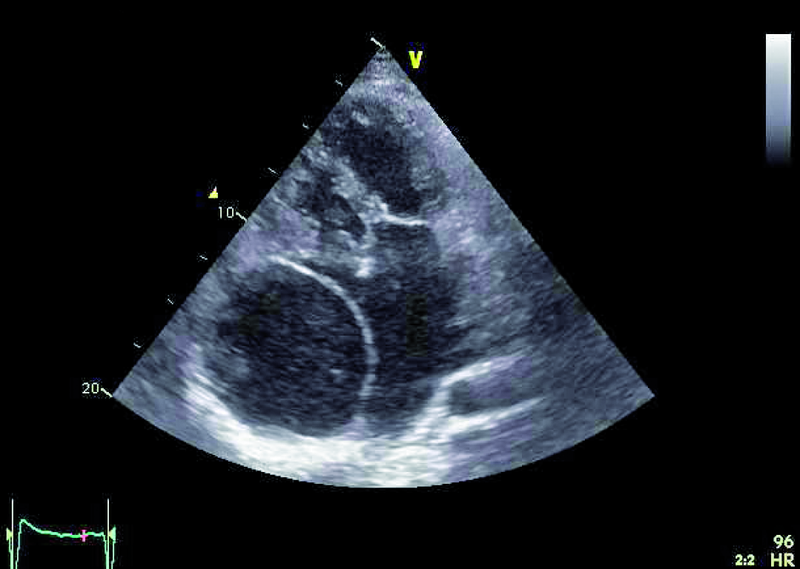

Mężczyzna, lat 31, z wrodzoną wadą serca o typie serca jednokomorowego, zastawkowego i podzastawkowego zwężenia tętnicy płucnej przeszedł w siódmym roku życia zabieg korekcji wady metodą Fontana-Linsa w ośrodku za granicą. Chory od kilku lat gorzej tolerował wysiłek. Rozpoznano napadowe, a następnie utrwalone migotanie przedsionków. Zdarzały się także obrzęki kończyn dolnych, powiększenie obwodu brzucha. Chory negował występowanie sinicy. W badaniu fizykalnym stwierdzono u niego szmer holosystoliczny nad sercem (3/6 w skali Levina), płyn w jamie opłucnej oraz wodobrzusze. Zwrócono uwagę, że w ostatnich latach saturacja spoczynkowa zmniejszyła się z 97 do 90%, a maksymalne zużycie tlenu w teście ergospirometrycznym wyniosło 13,8 ml/kg/min, co stanowiło 31% wartości należnej dla płci i wieku. Stwierdzono silnie wyrażone cechy zespołu enteropatii z hipoproteinemią. W chwili hospitalizacji leczony był dwoma środkami moczopędnymi, beta-adrenolitykiem oraz inhibitorem ACE. Otrzymywał także leczenie przeciwkrzepliwe. Wobec złego stanu ogólnego pacjenta wykonano cewnikowanie serca, stwierdzając ciśnienie w prawym przedsionku 13 mm Hg, średnie ciśnienie w tętnicach płucnych 14 mm Hg, opór płucny 0,2 j.W. Prawy przedsionek był w badaniach istotnie powiększony. Stwierdzano także poszerzenie żyły głównej dolnej (do 36 mm) z cechami samoistnego kontrastowania.

Operację Fontana, będącą rodzajem zabiegu paliatywnego, wykonuje się w celu korekcji zaburzeń hemodynamicznych towarzyszących wspólnej komorze. Celem operacji jest zmniejszenie przeciążenia objętościowego komory, ponieważ otrzymuje ona napływ zarówno z żył płucnych, jak i systemowych. Jest wiele rodzajów serca jednokomorowego. Najczęściej spotyka się zespół z atrezją trójdzielną, niedorozwojem lewej komory, zarośnięciem tętnicy płucnej, dwunapływową komorą lewą, dwuodpływową komorą lewą lub prawą. W podanym przykładzie można wyróżnić dwie zastawki przedsionkowo-komorowe, a więc krew wpływa do wspólnej komory (anatomicznie lewej) zarówno przez ujście trójdzielne, jak i mitralne, co dowodzi obecności komory dwunapływowej (ryc. 1-4). Celem operacji w tym wypadku było nie tylko oddzielenie spływu z żył systemowych, ale także zwiększenie całkowitej objętości krwi płynącej przez łożysko tętnic płucnych. Jak oceniać echokardiograficznie pacjenta po operacji metodą Fontana? Nie dziwi, że wspólna komora jest powiększona (ryc. 1, 2, 5), przerośnięta (ryc. 1, 2) i wykazuje upośledzoną kurczliwość. Jeśli wykształcone są dwie zastawki przedsionkowo-komorowe, należy ocenić każdą z nich, ponieważ fale zwrotne powodowane przez zastawki mogą zwiększać objętość komory i niekorzystnie wpływać na funkcję kurczliwą mięśnia. Niedomykalność zastawek przedsionkowo-komorowych (w podanym przykładzie umiarkowana [ryc. 5]) może także zwiększać ciśnienie w jamie lewego przedsionka, co zmniejsza konieczny dla wytworzonego zespolenia gradient ciśnień: żyła systemowa – tętnica płucna – lewy przedsionek. Wynikiem zmniejszania się gradientu może być narastanie ciśnienia w kanale Fontana (ryc. 1-3), pojawienie się hepatomegalii, przesięków do jam ciała, zespołu enteropatii z hipoproteinemią. Niemal u wszystkich chorych po operacji Fontana obserwuje się poszerzenie światła żyły głównej dolnej ze zwolnieniem przepływu krwi i zjawiskiem samokontrastowania się. Nie zawsze udaje się precyzyjnie uwidocznić morfologię wykonanego zespolenia. W tym wypadku mieliśmy do czynienia z tzw. starym jego rodzajem, polegającym na bezpośrednim połączeniu prawego przedsionka z pniem tętnicy płucnej bezpośrednio (ryc. 6). Metoda taka (Fontana-Linsa) stosowana była w latach 70. i 80. ubiegłego stulecia. W przypadku ciężkiego upośledzenia funkcji kurczliwej wspólnej komory, braku zwężenia w kanale Fontana i wykluczenia istotnych niedomykalności zastawek przedsionkowo-komorowych postępowaniem z wyboru pozostaje zabieg przeszczepienia serca, do którego chory został zakwalifikowany.